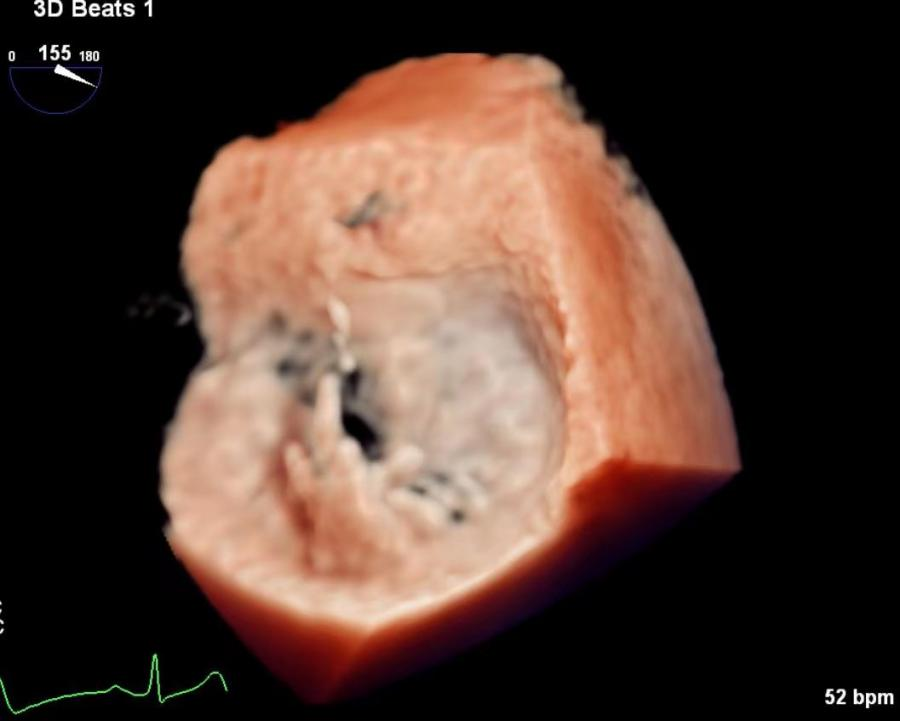

术前三维超声评估

图片